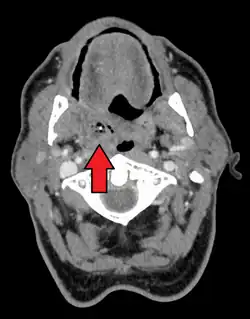

Absceso periamigdalar del lado derecho

Imagen de tomografía axial computarizada con un absceso periamigdalino derecho.

Se suele descubrir al inspeccionar la orofaringe (garganta) presentando hinchazón en un lado y en el paladar. La úvula puede estar desplazada.[8]